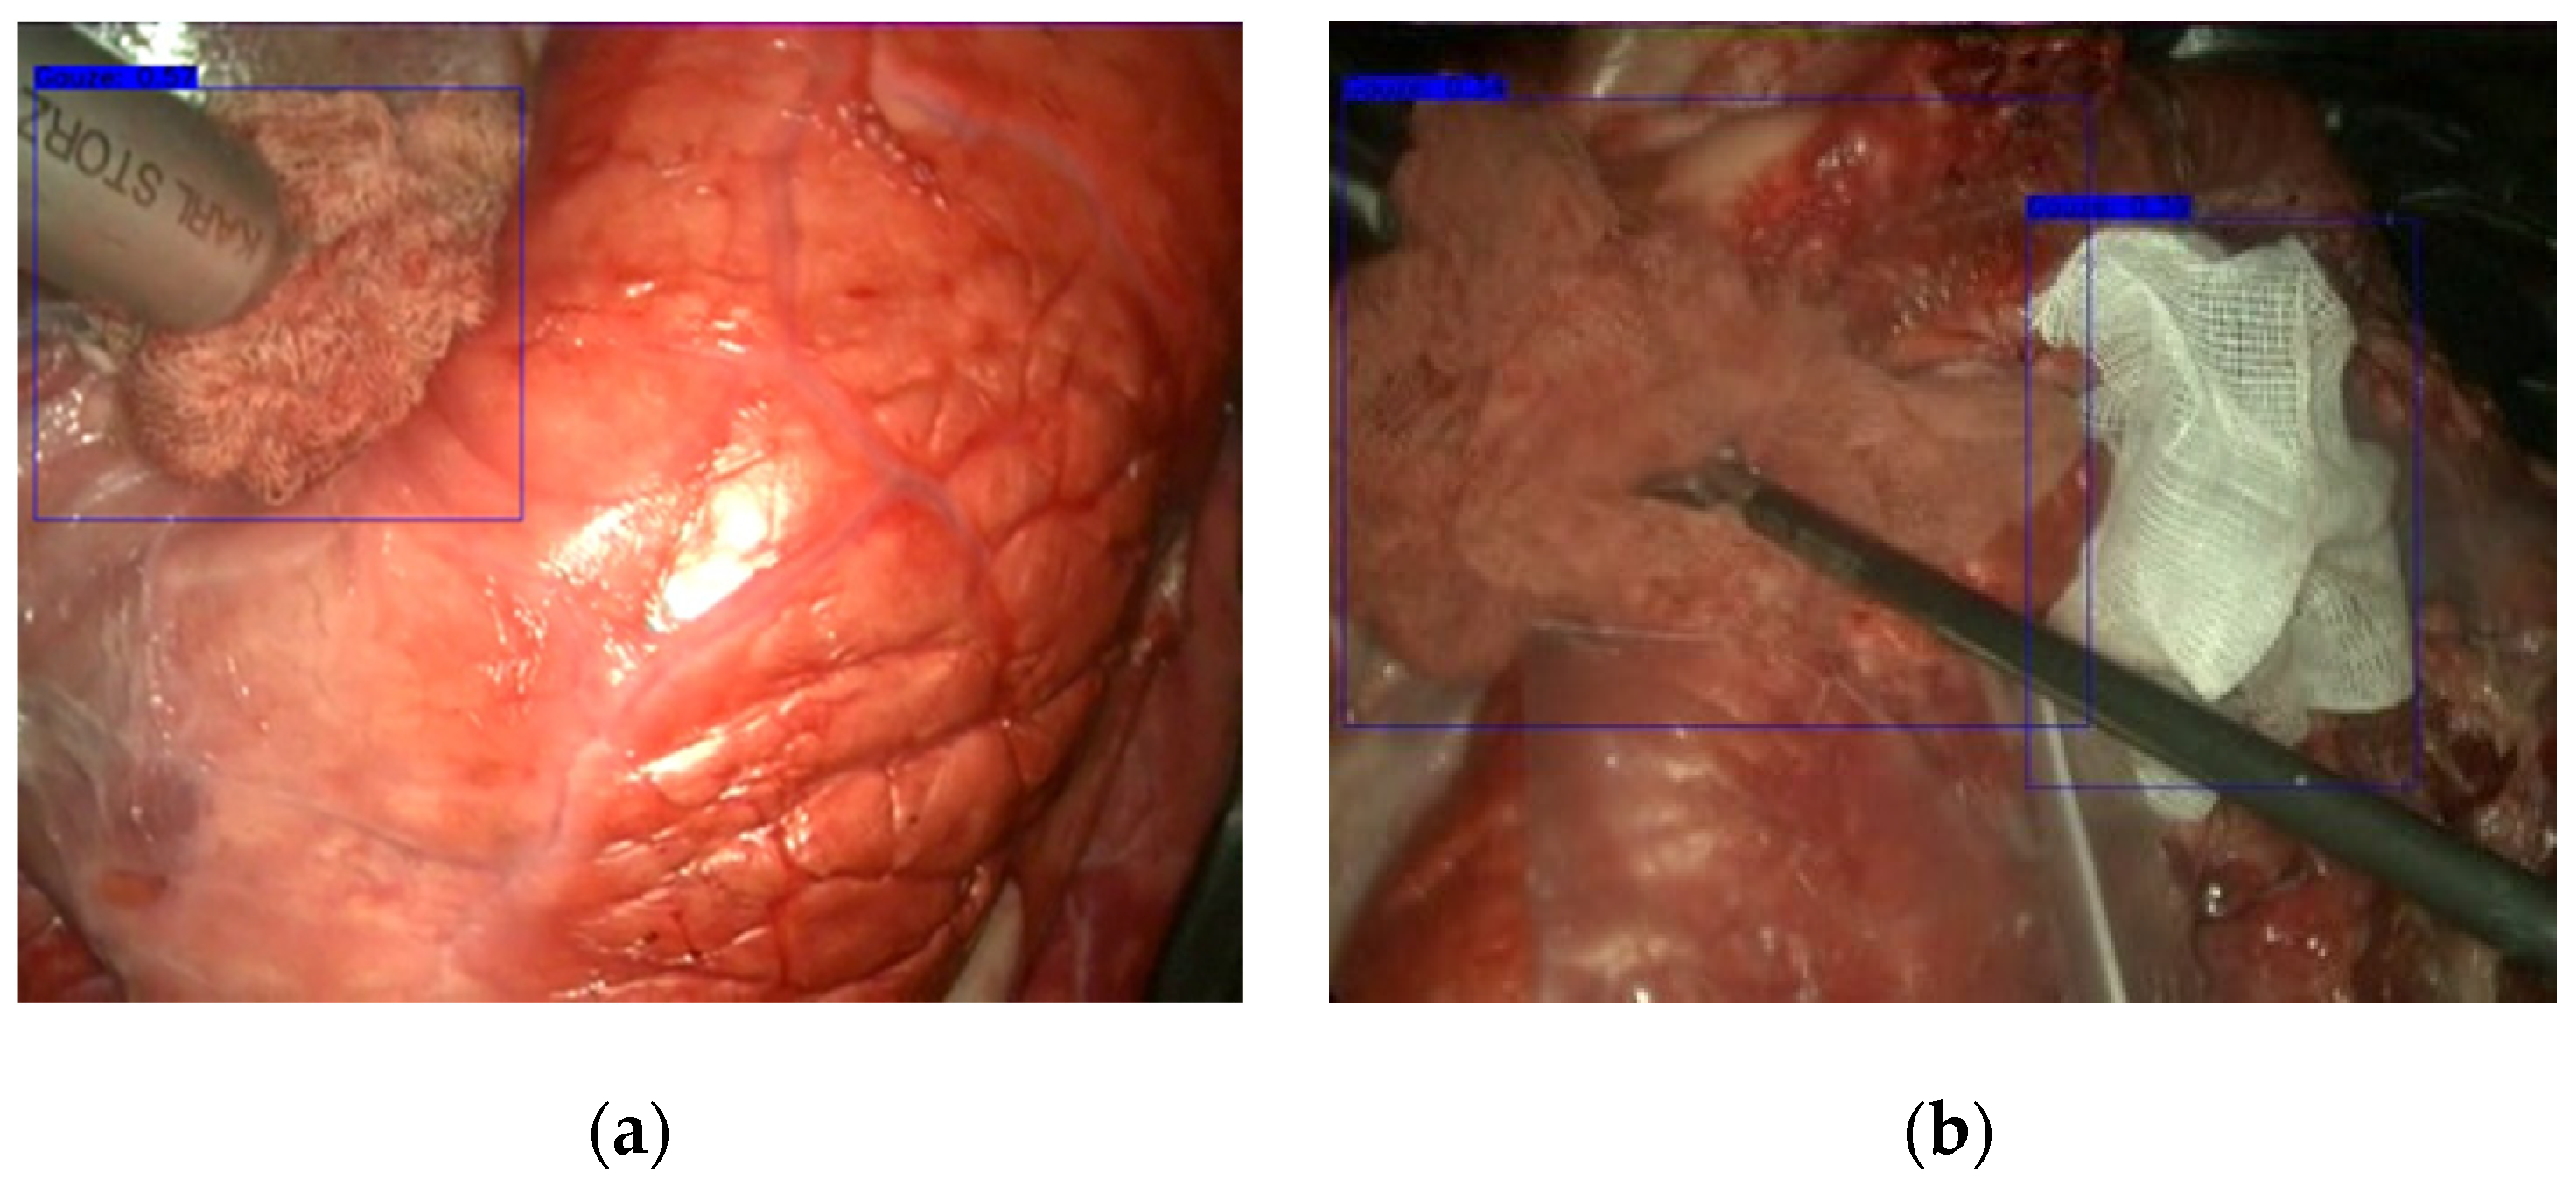

2.3. Gauze Detection

3.1. Gauze Detection